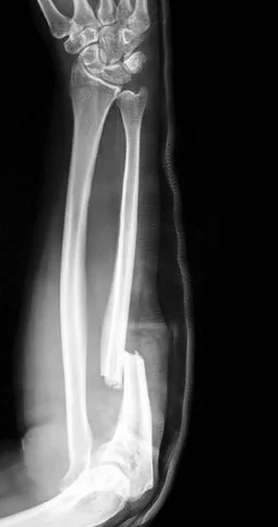

Intra-articular Distal Radius Fracture

- treated by anatomical open reduction, internal fixation and early mobilization